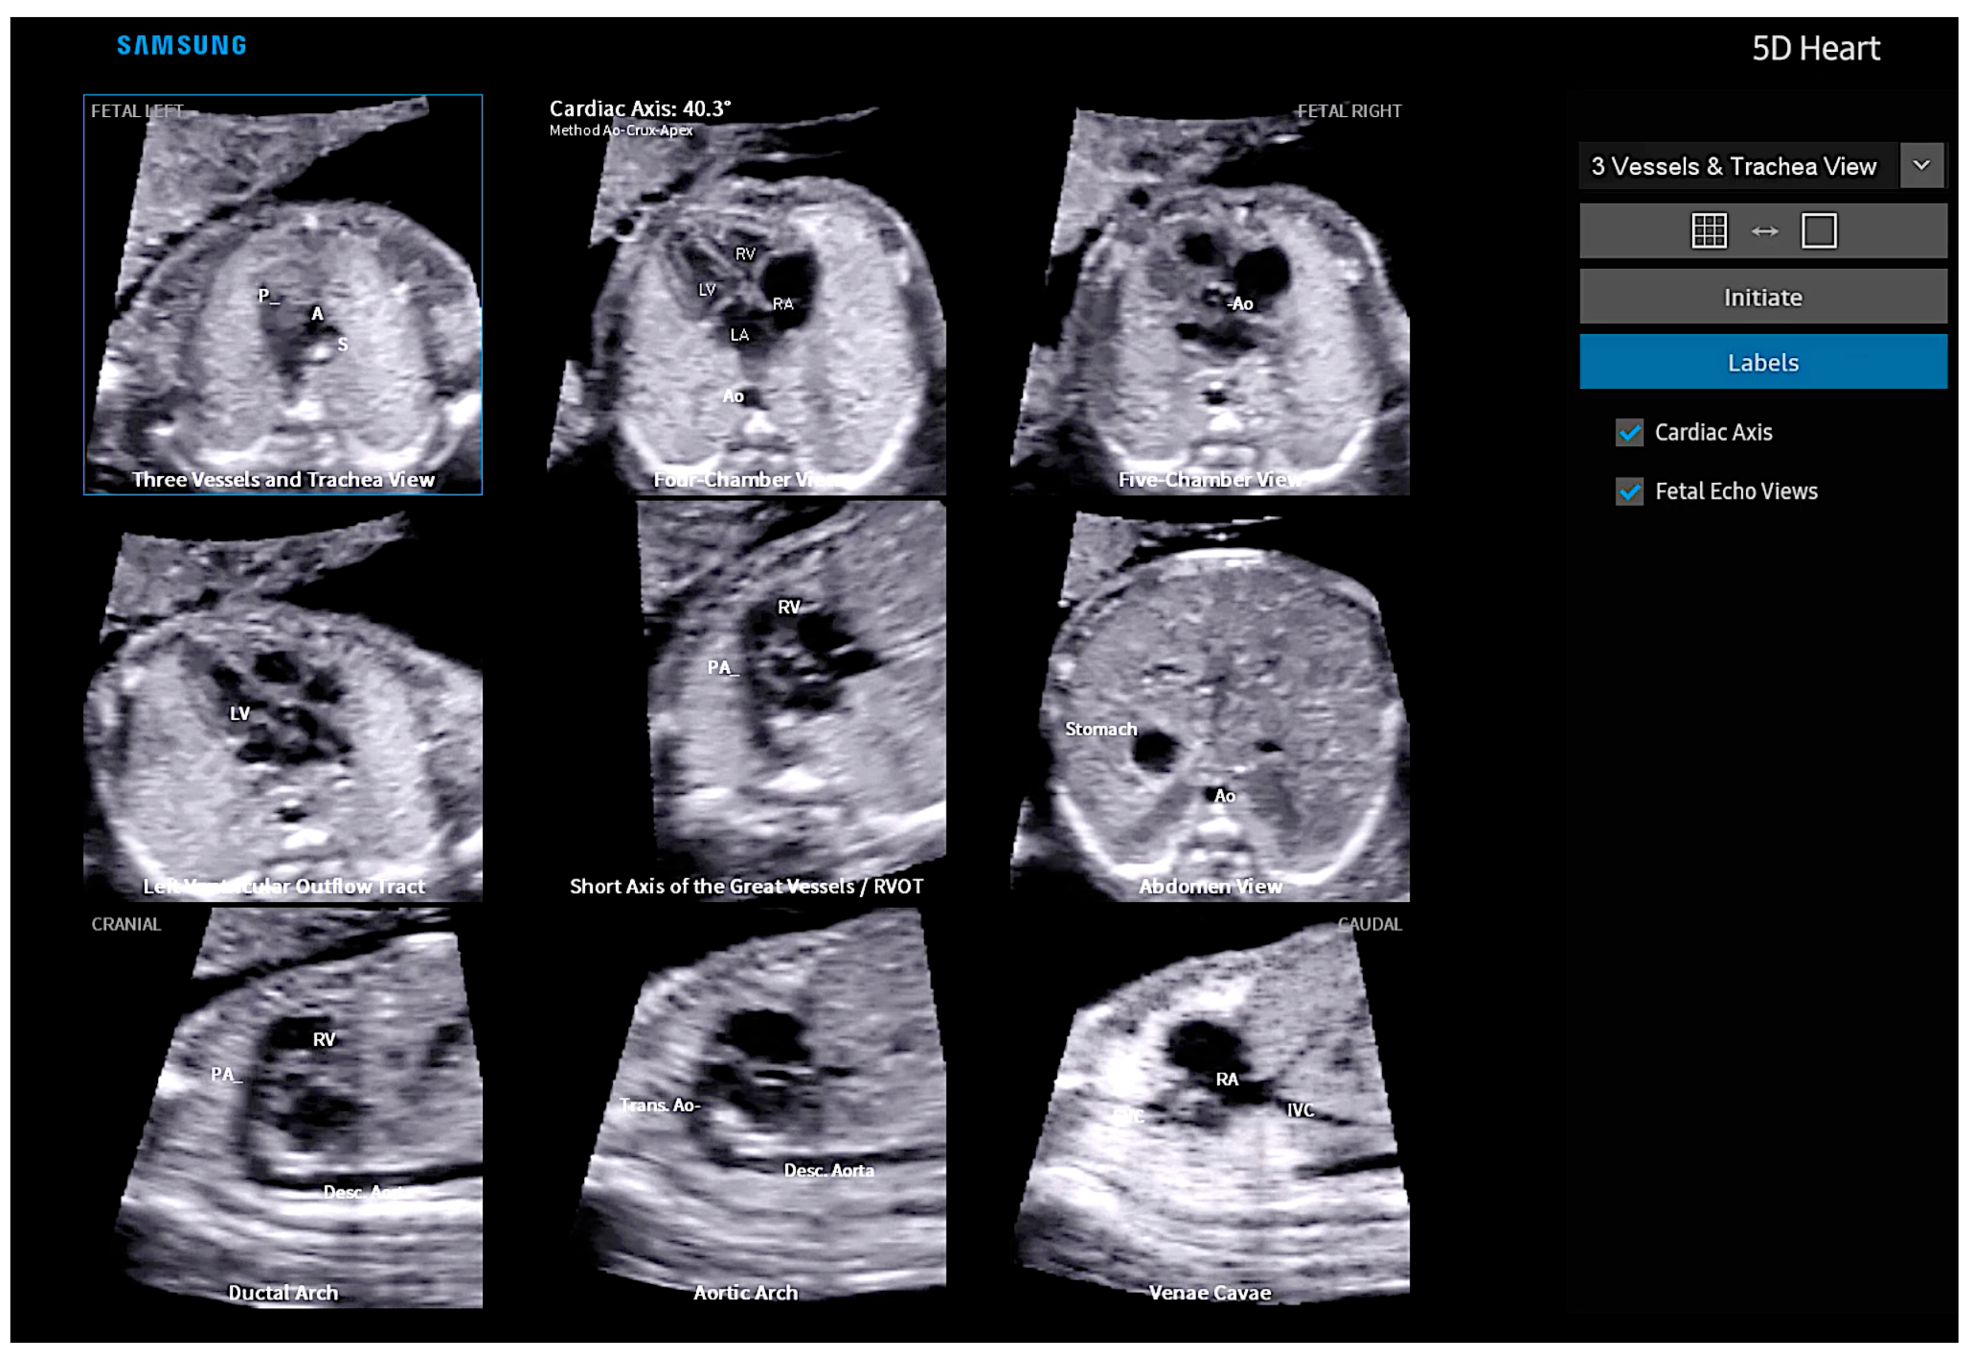

4. Fetal Intelligent Navigation Echocardiography “5D Heart”